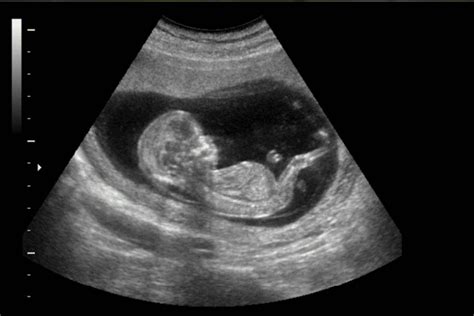

5. Observa a tu Bebé en la Pantalla

Las ecografías y otros estudios de imagen ofrecen información crucial sobre la salud de tu bebé, al tiempo que crean una conexión visual y tangible. Investigaciones sugieren que ver al bebé en estas exploraciones puede fortalecer el vínculo emocional con el feto.